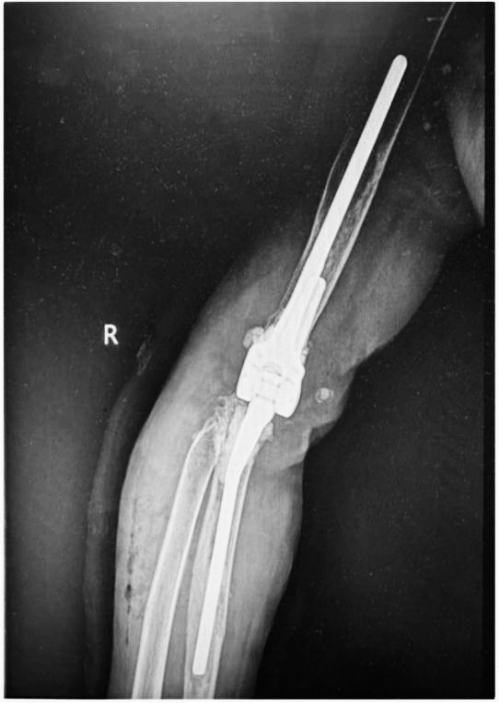

2024年3月25日,我院骨科中心关节外科病区团队成功完成一例复杂全部肘关节翻修术,使患者摆脱了肘关节活动受限的困扰,生活质量显著提高。这一技术的成功应用,标志着医院在关节治疗领域达到了新的高度,为众多关节损伤的患者带来福音。

与其他人工关节置换术相比,全肘关节置换术在设计和手术技术上要求更高。肘关节的复杂运动特性使得术后假体活动和稳定性的控制成为一大挑战。此外,假体在各种体位和活动中的松动、断裂和磨损风险,对手术医师的操作准确性与熟练度提出了严格要求。该患者术前肘关节假体肱骨侧及尺骨侧均几乎穿出骨皮质,髓腔形态异常,为确保手术成功,关节与足踝病区团队完善术前讨论,为该患者设计了个性化的3D打印肘关节假体,并提前模拟了手术假体安装过程。在王坤正教授的指导下,杨佩教授、王春生副主任医师经过精细操作,最终使这一例复杂肘关节置换术最终成功实施,使患者可以更快地恢复肘关节功能,进行正常的日常生活活动,提高生活质量。